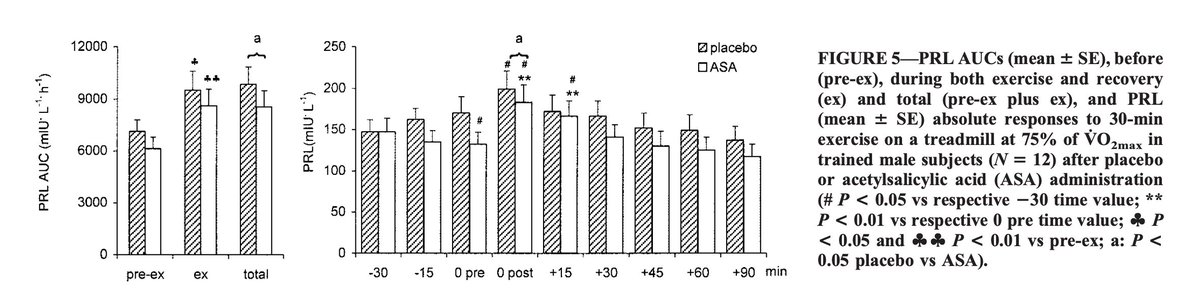

Aspirin seems to actually suppress the response of prolactin to stressors.

Prolactin is probably best known for being that feeling after ejaculation for men, opposing dopamine and giving this lethargic and unmotivated type of feeling.

Prolactin is probably best known for being that feeling after ejaculation for men, opposing dopamine and giving this lethargic and unmotivated type of feeling.